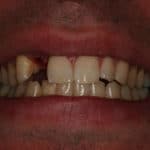

Anthony A.

This patient had only a few remaining infected teeth, but didn’t want to settle for just a denture.  Placed multiple implants and provided a secure fixed option which allowed him to not only chew better but to smile again.